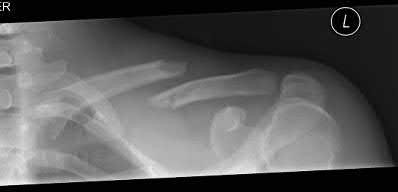

A 45-year-old male is involved in a high-speed motor vehicle collision and presents with the cervical spine radiograph findings typical of traumatic spondylolisthesis of the axis. Which of the following describes the primary mechanism of injury for this specific fracture pattern (Hangman's fracture)?

Correct Answer: Hyperextension and axial loading

A 'Hangman's fracture' is a traumatic spondylolisthesis of the axis (C2) involving fractures through the pars interarticularis. The classical mechanism of injury in modern trauma (e.g., unrestrained passenger hitting the windshield) is hyperextension and axial loading. Flexion-distraction typically causes Chance fractures, while flexion-compression typically causes anterior wedge or teardrop fractures.